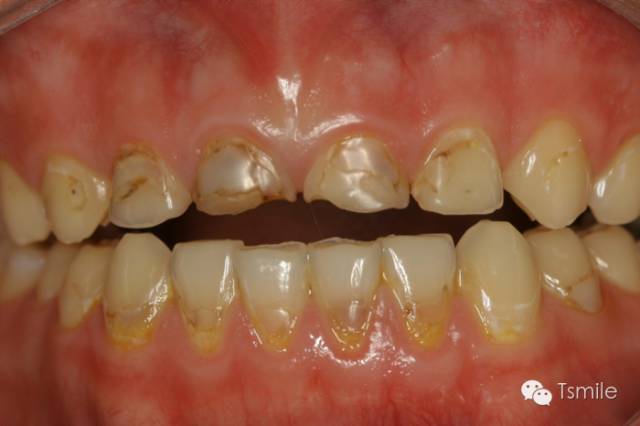

圖4: 神經(jīng)性貪食癥導(dǎo)致的上頜前牙舌側(cè)重度磨耗

神經(jīng)性貪食癥是患者由于心理性原因在飲食后自我催吐,混有胃液的嘔吐物進(jìn)入口腔內(nèi),接觸牙齒表面,對(duì)牙齒硬組織造成嚴(yán)重酸蝕脫礦。由于患者在嘔吐時(shí)的特定體位,神經(jīng)性貪食癥導(dǎo)致的牙列重度磨耗主要發(fā)生于上前牙的舌側(cè)、或者累積上頜前磨牙的舌面。